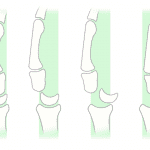

- Acute comminuted scaphoid waist fracture with midcarpal dislocation

- Midcarpal dislocation